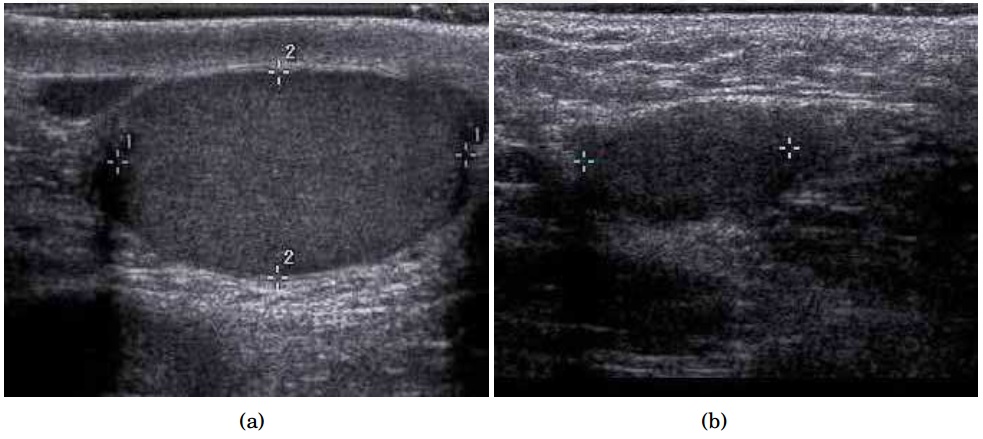

양쪽 모두 촉지되지 않는 고환의 소수 사례에서는 고환을 찾고, 기능을 평가하며, 추가적인 문제를 배제하기 위한 추가 검사가 종종 유용하다. 음낭 초음파 또는 자기 공명 영상을 방사선 전문의가 수행하고 해석하면 고환을 찾고 자궁 부재를 확인할 수 있다. 초음파에서 잠복고환은 일반적으로 작고, 반대쪽 정상 고환보다 에코성이 낮으며, 일반적으로 서혜부에 위치한다. 컬러 도플러 초음파를 사용하면 잠복고환의 혈관 분포가 빈약하다.